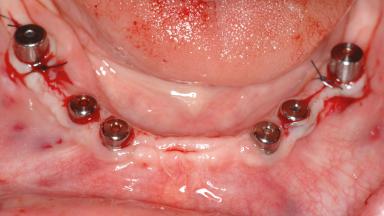

A 47-year-old woman who had suffered from aggressive periodontitis requiring a number of periodontal interventions over more than 10 years was referred by her general dental practitioner and periodontologist for bone augmentation and implant therapy. Her failing dentition had already been scheduled for extraction. The patient expressed a desire for implant-supported fixed restorations and esthetic improvement of her lower face. She had agreed to consult with a maxillofacial surgeon after the referring dentist had suggested bone augmentation. An initial examination by the maxillofacial surgeon revealed mobility of all residual teeth in a patient who was very unhappy with the function of her removable partial dentures. Due to periodontally migrated flaring teeth and loss of occlusal support, the vertical dimension of occlusion was dramatically reduced. The patient was displeased with her lower face because of deepened nasolabial, commissural, and supramental folds.

# of Implants 14

Bone Augmentation Horizontal|Sinus Floor Elevation|Staged|Vertical

Augmentation Materials Autogenous chips|Autogenous block(s)|Xenogenous|Membrane